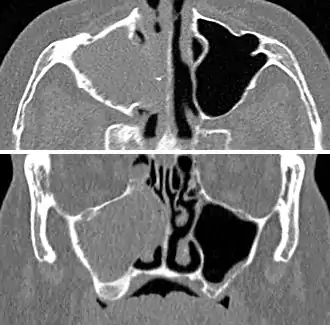

For cases of maxillary sinusitis, limited field CBCT imaging, as compared to periapical radiographs, improves the ability to detect the teeth as the sources for sinusitis. A coronal CT picture may also be useful.[37]

Chronic

For sinusitis lasting more than 12 weeks, a CT scan is recommended.[54] On a CT scan, acute sinus secretions have a radiodensity of 10 to 25 Hounsfield units (HU), but in a more chronic state they become more viscous, with a radiodensity of 30 to 60 HU.[56]

.jpg.webp) CT of chronic sinusitis

CT of chronic sinusitis CT scan of chronic sinusitis, showing a filled right maxillary sinus with sclerotic thickened bone.

CT scan of chronic sinusitis, showing a filled right maxillary sinus with sclerotic thickened bone. MRI image showing sinusitis. Edema and mucosal thickening appears in both maxillary sinuses.